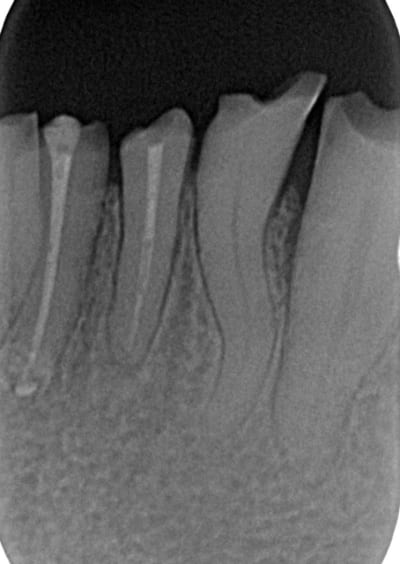

la radio des dents 12-13 illustre parfaitement mes doutes:

Après avoir vu en conf Genon procéder à des chir paro (gingivectomie à biseau ext + plastie osseuse) sur les secteurs antérieurs, chez des bruxos pour gagner de la surface dentaire (en vue de faire les CCM par la suite) sans augmenter de façon inconsidérée la DV, je me disais que j'aurai pu proposer la même solution chez ce patient.

Oui mais..., c'était avant de faire la radio où on voit de petites racines et bien coniques par dessus tout... bref tout ce qui peut être défavorable et contre-indiqué cette solution... :-(

- Y a t il vraiment une réelle perte de DV?

- n'y a t il pas une compensation par égression?

bé oui. voir les procés alvéolaires mxillaires. Je pensais faire une chir paro, tailler dans la viande et dans l'os pour réduire cette compensation mais après j'aurai plus beaucoup d'os autour des dents (qui ont de petites racines)... donc????